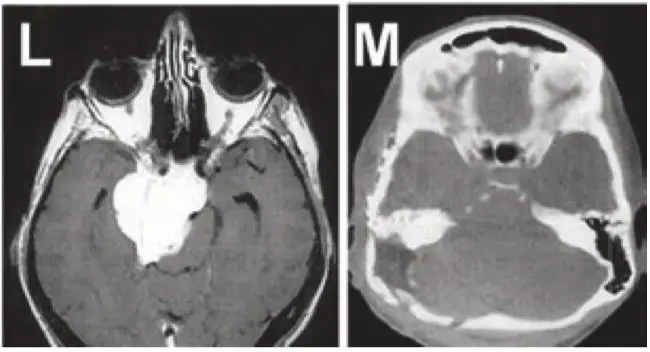

图L+M:岩斜区脑膜瘤患者,术前术后的影像对比